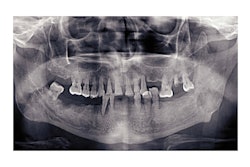

The study involved 172 people with an average age of 67 who did not have memory problems at the beginning of the study. Participants had dental exams and took memory tests in addition to undergoing brain magnetic resonance imaging to measure the volume of their hippocampus both at the beginning of the study and again four years later.

In addition, researchers counted the number of teeth for each participant and checked for gum disease by assessing periodontal probing depth, a measurement of the gum tissue.